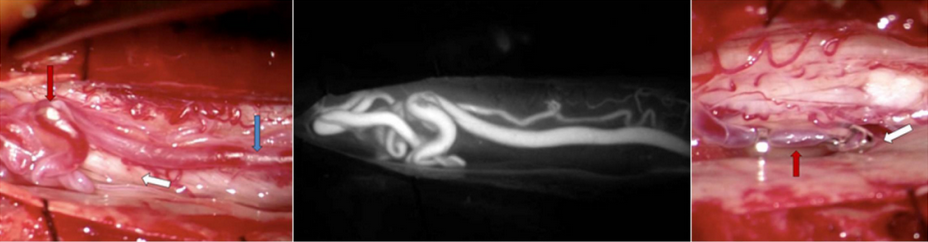

Figure 4a: Intraoperative view of a Type 1 spinal dural fistula surgery. The enlarged vein (blue arrow) laying on the spinal nerves (white arrow) is abnormally filled with red arterial blood leading to an abnormal tangle of veins (red arrow). Figure 4b: The same view of the abnormal vessels as seen with an intraoperative ICG angiogram. Figure 4c: The abnormal vein has been clipped just as it enters the spinal dura (white arrow) to stop the high arterial flow. Upstream, the vein loses its enlarged red shape and appropriately softens (red arrow) and becomes a blue-purple color like normal veins. This technique cured the fistula and the patient improved greatly.